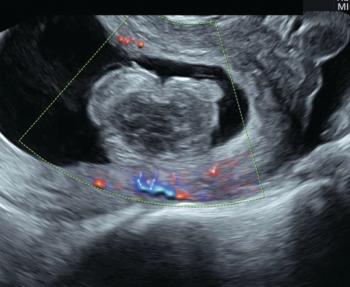

Ultrasound is a Critical Tool of Managing Miscarriage

ByBryann Bromley, M.D.,Thomas Shipp, M.D., RDMS

Ultrasound technology can be an indispensable tool for the management of suspected early pregnancy loss.